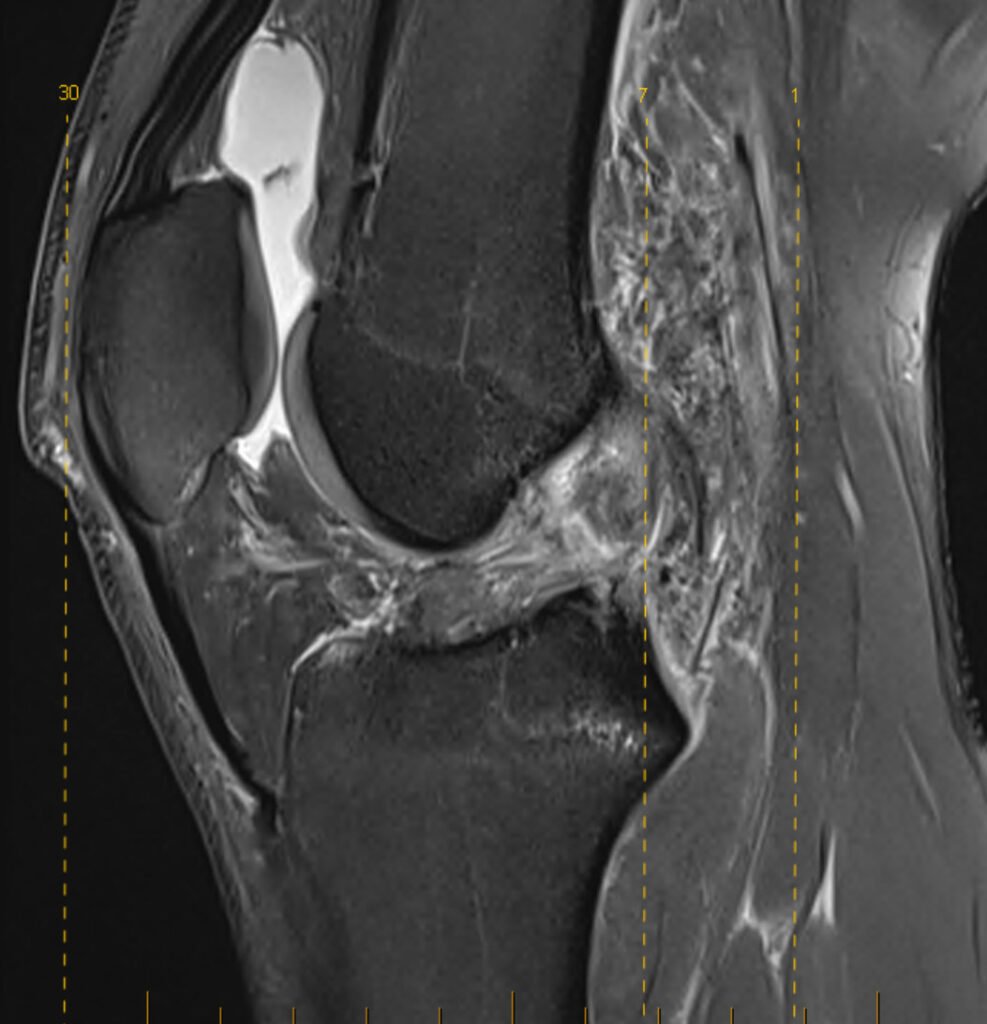

Dr Awwad will begin with a detailed history and physical examination to assess your knee stability, swelling, and range of motion. Specific clinical tests such as the Lachman test and pivot shift test help assess the integrity of the ACL.

- X-rays: Used to rule out fractures or associated bony injuries

- MRI scan: The most accurate way to confirm a complete or partial tear and assess other internal knee injuries such as meniscal tears or bone bruising

A prompt and accurate diagnosis helps determine whether non-surgical or surgical treatment is most appropriate.